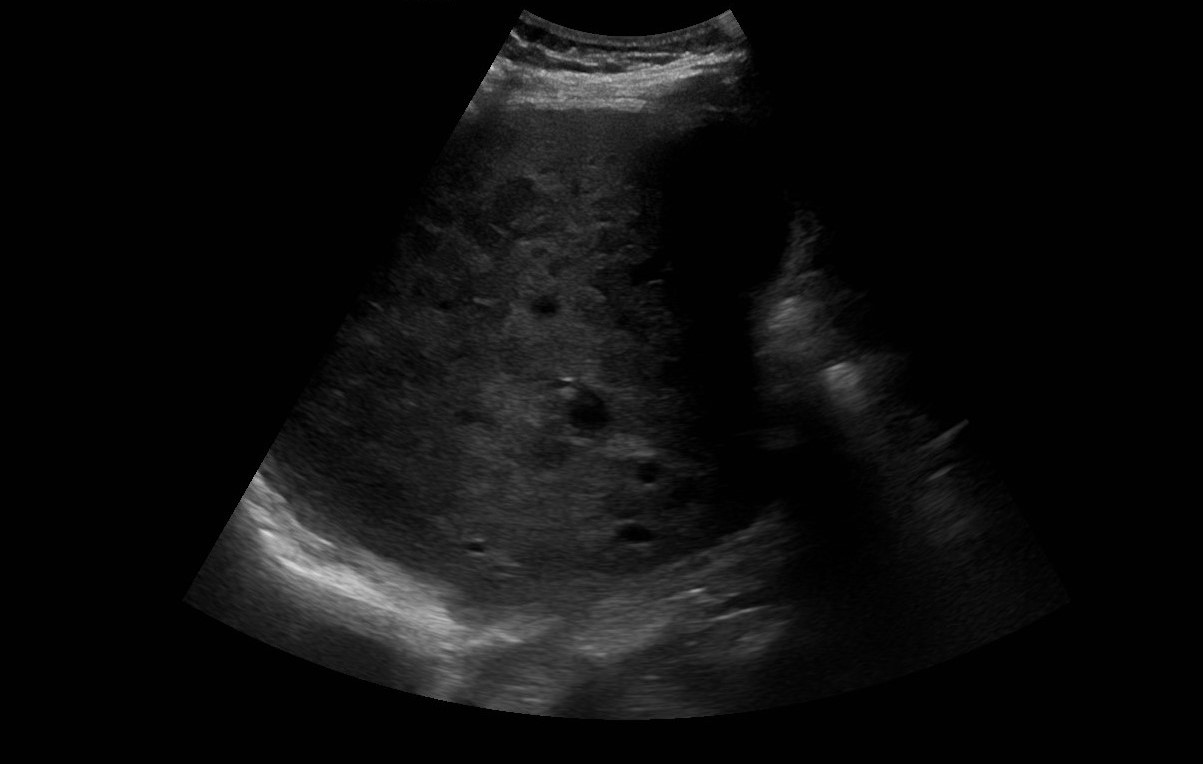

Se realiza analítica con perfil hepático: GOT 100, GPT 55, GGT 454 y FA 218 con proteína C Reactiva 146 y Lactato deshidrogenasa 1.227; por lo que se realiza ecografía clínica a pie de cama con hallazgo de múltiples imágenes hipoecoicas en parénquima hepático.